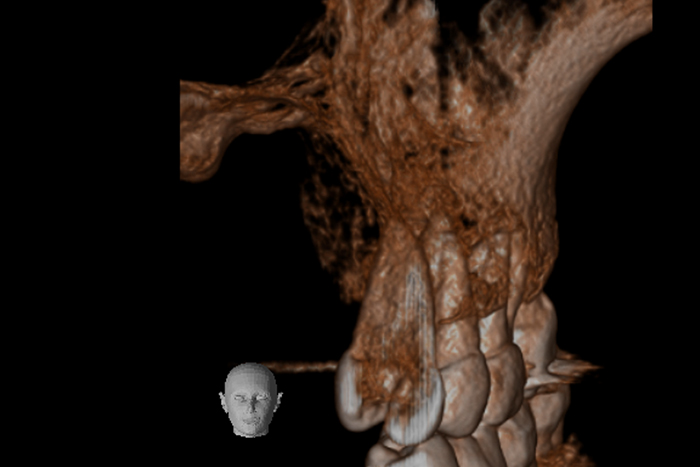

根の横に誤った穴をあけてしまい、気づかずに薬を入れてしまっている。また、器具が破折し、根の先に飛び出ている。

精密根管治療治療終了時歯の側面の穴と根尖はMTAにより緊密に封鎖した。